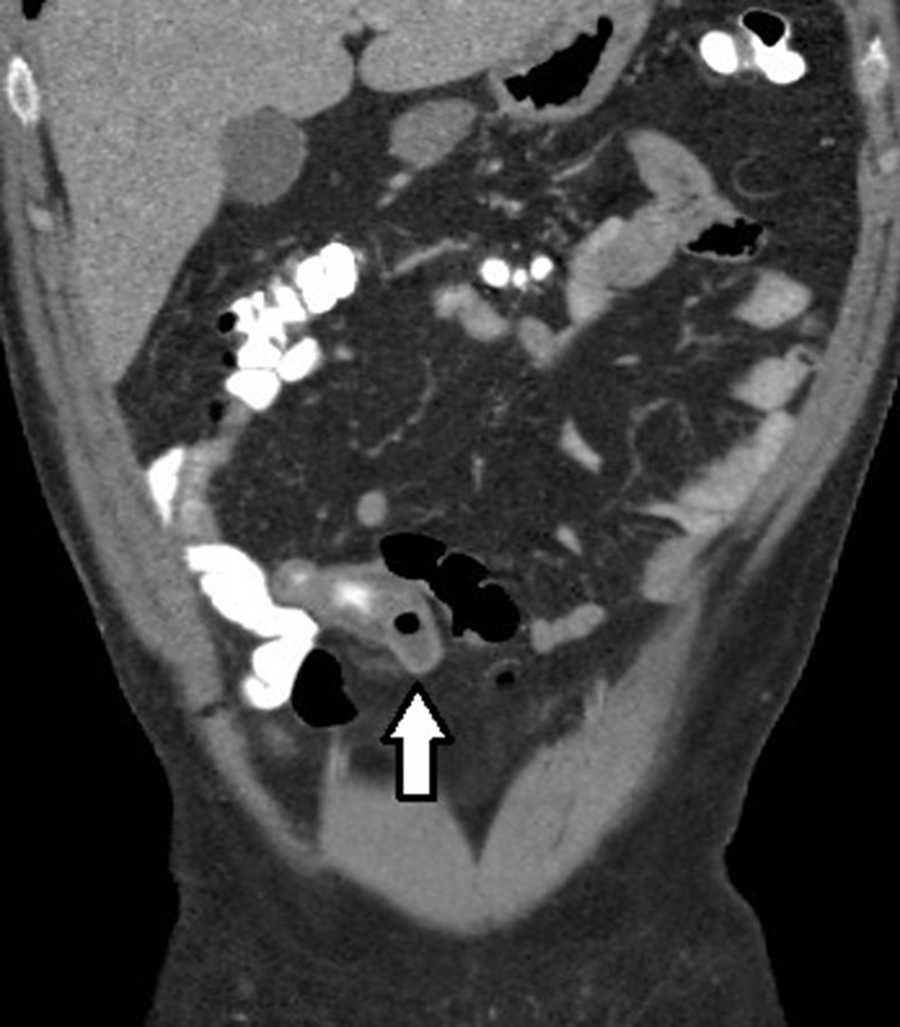

Obstrucción intestinal (3%): se observa obstrucción secundaria al proceso inflamatorio peridiverticular, con un área con cambio de calibre en el punto de partida del divertículo complicado. En el divertículo de Meckel, esta complicación ocurre en el 40% de los casos y se produce por una banda mesodiverticular, un vólvulo del divertículo, un mecanismo de invaginación (fig. 6) o por la extensión a un saco herniario8.